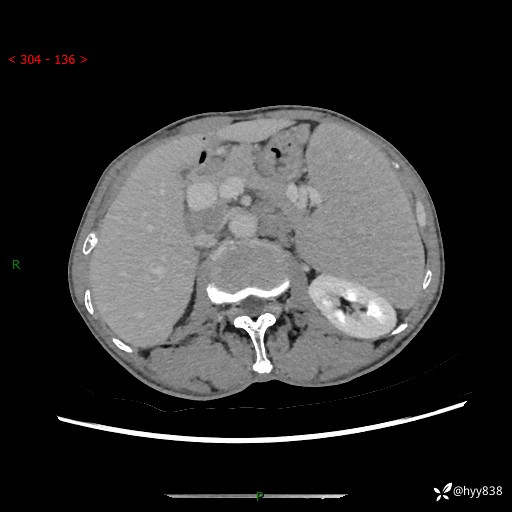

老年男性,脾大并脾脏弥漫粟粒状低密度,淋巴瘤 VS 肉芽肿 VS 血管瘤---结果公布

简要病史: 患者于3月前无明显诱因出现脾大,伴腹部轻微不适,具体不详,无腹痛、腹泻、腹胀,无头晕、头痛、乏力,无恶心、呕吐、呕血,无胸闷、气短、胸痛不适

上腹部CT平扫+增强